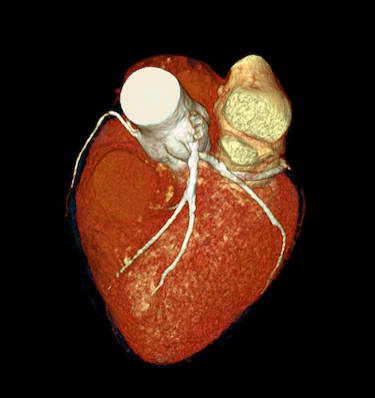

Case Study (70% LAD Block)

Case Study (70% LCX Block)

Case Study (Stent - LAD & LCX)

Case Study (Triple Vessel Block)

Cardiac CT

CARDIAC CT. Explained.